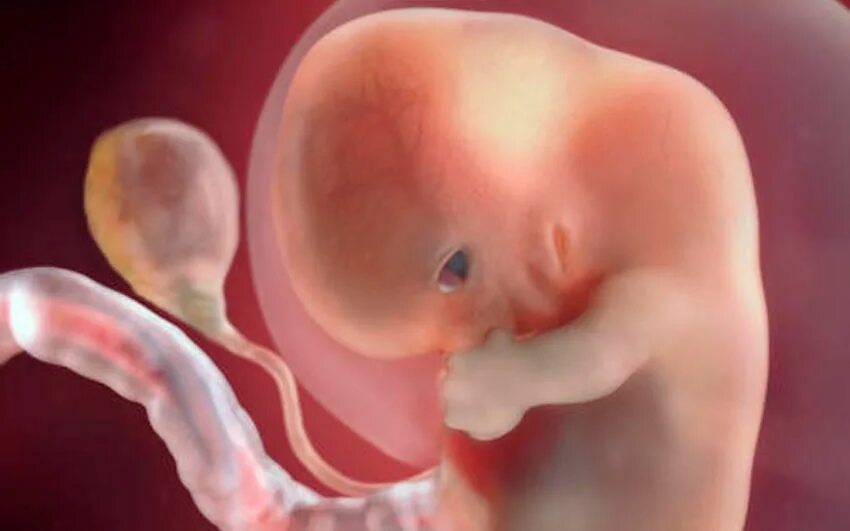

Как выглядит ребенок в 8 недель